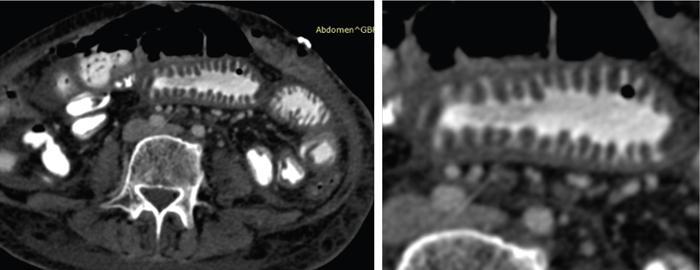

SMALL BOWEL IMAGING Poonam Narang, Himanshu Gupta The small bowel is a long tubular hollow abdominal viscus thrown into intricate folds and loops and packed into the abdominal cavity. It is approximately 5–7 m in length and extends from the gastric pylorus up to the ileo-caecal valve. It is anatomically divided into three parts: duodenum (meaning ‘in twelves’ as its length is roughly equal to the width of 12 fingers), jejunum (meaning ‘fasting’ as it was usually found empty after death) and ileum. The duodenum measures 20–25 cm in length and extends from gastric pylorus to the ligament of Trietz. It is a fixed ‘C’-shaped structure that cradles pancreatic head in its concavity. First part of the duodenum is a triangular conical structure with its base communicating with gastric antrum. Its apex points to the right and cranially, in close apposition with the gall bladder and the under surface of the liver. Second part of duodenum is almost vertical, lying in the right paravertebral gutter. The common bile duct courses obliquely posterior to it and drains at a papilla at its medial wall (the Ampula of Vater), after joining with the main pancreatic duct. Third part is horizontal, crossing the midline between the superior mesenteric artery (SMA) and aorta from right to left, caudal to pancreatic neck. Fourth part is again almost vertical, ascending left of the spine almost to the level of duodenal bulb and transitions to jejunum at duodenojejunal (DJ) flexure. Duodenum is mostly a retroperitoneal structure while the rest of the small bowel acquires a mesentery at the DJ flexure. The jejunum and ileum are intraperitoneal structures, suspended in the abdominal cavity from the posterior abdominal wall by the free end of their ‘fan-shaped’ mesentery and are thus relatively mobile. Though considered a part of small bowel, duodenum differs from the rest of the small bowel in structure as well as function. Plethora of the diseases that affect duodenum are distinct. Peptic ulcer disease affecting the first part does not affect the rest of the small bowel. Most other diseases affecting the duodenum arise from the surrounding structures like pancreas, gall bladder, bile duct, liver and the hepatic flexure of colon. Hence, on imaging, duodenal abnormalities should prompt a search for pathologies of the surrounding organs. While duodenum is structurally a distinct segment, the structural transition from jejunum to ileum is seamless, with no external demarcating point. Histologically, and also on imaging, all three segments have clear identities. Their mucosal lining, folds and presence of submucosal lymphoid follicles are allocated in accordance with their specific functions. Jejunal loops occupy left hemiabdomen and ileal loops, with ileo-caecal junction, lie in the right lower abdomen. Jejunum is about two-fifths of the length of the small bowel, and the ilium forms the rest of the three-fifths of the entire 5–7 m. ‘Terminal ileum’ is a term arbitrarily but commonly used in clinical practice to denote the portion of ileum just proximal to ileo-caecal junction harbouring abundant lymphoid tissue in its walls and playing host to a number of pathologies. At ileo-caecal junction, the ileum joins the caecum obliquely. A valve-like mucosal fold regulates the flow of digested food into the colon and prevents its reflux back. Its efficiency in preventing reflux is quite inconsistent in a large percentage of subjects. The arterial supply of the duodenum is by the branches of hepatic artery (branch of Celiac Axis artery), till the proximal half of second segment (marked by the Ampula of Vater); and by branches of the superior mesenteric artery beyond that point. Duodenal branches of respective superior and inferior pancreatico-duodenal arteries make an arcade along the medial margin of duodenum in the pancreatico-duodenal groove. The rest of the small bowel is supplied by the superior mesenteric artery and its branches while venous drainage is via superior mesenteric vein and its tributaries. These vessels traverse the mesentery, between the twofolds of the peritoneum from the posterior abdominal wall to reach the small bowel forming multiple arcades of vessels within the mesentery. Straight arteries, called the Vasa Recta, arise from the terminal arcade and enter the bowel wall, along its mesenteric border. Disease processes involving the specific artery affects the respective bowel segment that it supplies. Ischaemia, infarction and haemorrhage can be attributed to and localized correctly based on the relevant vascular anatomy. Inflammatory diseases cause engorgement of Vasa recta; and at times, identifying them as a lead point, one is able to localize the involved bowel segment correctly. Vascular ischaemia affects the antimesenteric part of the bowel earlier in the course of the disease. Therapeutic procedures too can be appropriately planned based on the vascular territory of the affected bowel segment. The mesentery forms a fan-shaped suspensory support, tethering the small bowel to the posterior abdominal wall, along a line running obliquely from ligament of Trietz (in LUQ) to ileo-caecal junction close to superior part of right sacro-iliac joint (in RLQ). This ‘root of mesentery’ averages about 15–20 cm in length. It is closely wrapped around small bowel loops and merges with the serosa. All lymphatic and vascular channels supplying to and draining from the small bowel traverse within the mesentery. Thus, pathology originating in one often affects the other by contiguity, haemodynamic alteration or haemo-lymphatic spread. The normal mesentery sandwiches a layer of fat between its two leaves. On imaging, it provides a good background against which identification of pathologies of fluid density (oedema) or soft tissue density (phlegmon, lymph nodes, masses) can be made. Mesenteric oedema often becomes the smoke leading up to the fire, for example: focal oedema adjacent to the site of an otherwise invisible bowel wall perforation. On ultrasound, such tell-tale inflammation is seen as an increase in the echogenicity of mesenteric fat adjacent to the site of bowel pathology. On CT, the hypodense fat becomes hyperdense whenever any pathological change occurs. Delineation of mesenteric vessels is also facilitated due to surrounding hypodense fat. Engorged Vasa recta are easy to identify on imaging as they stand out against the surrounding fat in the mesentery. Similar imaging findings can be extrapolated to MR as well. Similar to the rest of the gastrointestinal tract, the small bowel wall comprises four layers (strata) – from within outwards being mucosa, submucosa, muscularis propria and serosa. Mucosal folds (Valvulae Conniventes) and further finger-like projections of mucosa (Villi) help dramatically increase the surface area for absorption. Only valvulae conniventes are seen radiologically as concentric rings measuring 2–3 mm. The bowel wall measures 1–2 mm when distended and 2–3 mm when collapsed symmetrically in its entire circumference. Increased bowel wall thickness (in the background of adequate luminal distension) is a commonly used marker of pathology. Understanding how different pathologies target specific sites within the micro-structure of bowel wall, along with length of bowel involvement, could be helpful in drawing conclusion regarding the etiopathogenesis. For example, short segmental disruption of the entire thickness of bowel wall favours a unifocal, infiltrative pathology-like malignancy. Long segment submucosal oedema with preserved mucosal integrity/enhancement may be a haemodynamic phenomenon as in portal enteropathy or reactive as in infective enteritis. Depth and invasiveness of a disease process can be monitored for activity/progression, especially on imaging modalities like ultrasonography and MRI. The innermost anatomic layer of small bowel wall, its mucosa forms the absorptive surface which transports nutrients from the lumen into blood/lymph. Pathologies affecting the mucosa cause reduction (shortening) in the available area of absorption – the so-called short bowel syndrome. A variety of metabolic derangements can accompany the nutritional deficiencies caused thereby. Many other inflammatory and infiltrative diseases like lymphomas cause various alterations in the appearances of mucosal folds. Reduction, blunting, flattening, thickening, clubbing, nodularity, polypoid formation, etc. are various imaging appearances of the disease processes affecting the mucosal surface (Figs. 8.3.1.1–8.3.1.3). These abnormalities can be local, segmental, regional or generalized; involving the entire circumference, mesenteric or antimesenteric regions. The radiologist’s role thus lies in identifying the presence, location and extent of mucosal abnormality in addition to suggesting a possible aetiology based on the specific clinical settings. Small bowel has no sensory or motor nerve supply and is regulated by autonomic nervous system for its motility, secretions and absorption. Branches from vagus nerves and from dorsal sympathetic ganglion also traverse the mesentery to innervate the bowel wall at the mesenteric border. During the third week of intrauterine life, the process of ‘gastrulation’ results in formation of three basic layers, namely ectoderm, mesoderm and endoderm, which eventually evolve and differentiate into tissues and organs of all systems. Bowel, along with hepatobiliary and pancreatic system, develops from the ‘primitive gut tube’ that is formed when the endoderm folds upon itself. It then differentiates into three sections: foregut, midgut and hindgut. By 4–6 weeks, the rapidly growing intraabdominal organs outgrow the coelomic cavity. The midgut undergoes physiological umbilical herniation and rotation and then herniates back into the abdomen by the 10th week. Subsequently, the developed midgut organs undergo peritoneal incorporation and fixation to occupy their respective intraabdominal positions. This process takes place in three stages, and interruption at each stage results in specific anomalies of malrotation and peritoneal fixation. During the first stage, from week 6 to week 10, the midgut herniates ventrally into the umbilical cord in a vertical loop configuration. This loop has the superior mesenteric artery in the centre dividing the midgut into a prearterial (jejuno-ileal) segment superiorly and a postarterial (caeco-colic) segment inferiorly. This loop rotates 90 degree counter-clockwise, with superior mesenteric artery as its axis. The prearterial segment comes to lie to the right and the postarterial segment to the left in a horizontal plane. The second stage, from week 10 to week 12, results in a further 90-degree counter-clockwise rotation, and the small bowel loops now are positioned under the postarterial segment. By the end of the 10th week, the abdominal cavity grows large enough to accommodate the entire length of the foetal bowel. As the bowel loops now return to the abdominal cavity, the small bowel returns first followed by the large bowel. Subsequently, the small bowel loops make their final 90-degree counter-clockwise rotation, bringing the D-J junction to the left of the spine, while the colon makes a 180-degree rotation in the same direction to place the caecum in the right lower quadrant of the abdomen. Thus, by the end of stage II, the midgut derivatives have undergone a total 270-degree rotation (including the initial 90-degree rotation) with DJ junction to the left of midline, caecum in the right lower quadrant and transverse colon crossing in front of the duodeno-jejunal junction. Vitello-intestinal duct (VID) gets obliterated by the ninth week. The third stage (from 12 weeks until term) involves fixation of the mesenteries to the posterior abdomen. The completed normal rotation of the bowel produces a long mesenteric attachment for small bowel, extending from ligament of Treitz at the D-J junction in left upper quadrant to the ileo-caecal valve in right inferior quadrant known as the ‘root of mesentery’. The dorsal mesentery of some portions of the gut, like pancreas, duodenum, ascending and descending colon, becomes incorporated into the posterior abdominal wall, making these segments secondarily retroperitoneal (Figs. 8.3.1.4–8.3.1.6). Understanding of chronological embryology helps one to interpret respective imaging features of developmental anomalies and also to look for their associations. During imaging of a suspected case of malrotation, position of DJ flexure, ileo-caecal junction, relative location of jejunal and ileal loops and relation of superior mesenteric artery to the accompanying vein help in reaching the correct conclusion. It should be kept in mind that certain diseases (notably the celiac disease and other malabsorption syndromes) may invert the imaging morphology of jejunum and ileum leading to erroneous diagnosis. Evaluation of orientation of superior mesenteric vessels and the duodeno-jejunal junction would help resolve any ambiguity in such cases (Figs. 8.3.1.7 and 8.3.1.8). Developmental malrotation is often a precursor to small bowel volvulus, or obstruction by extrinsic bands in neonates and infants. In adults, on the other hand, often the malrotations are by themselves, asymptomatic. They get identified only incidentally, or while looking for symptoms due to their associations. Preduodenal peritoneal bands, commonly called as the Ladd’s bands, causing external compressions resulting in bowel obstruction are less common. Often, peritoneal fenestrations and deep fossae, associated with developmental midgut malrotations, present with internal bowel herniations like various para-duodenal and mesenteric herniations. One must be aware of their associations, so as to make the correct interpretation. Internal hernias may be a cause of intermittent postprandial abdominal pain, when reducible; or may result in acute bowel obstruction. They are identified by abnormal location and clumping together of the relatively mobile small bowel loops. High degree of suspicion and knowledge about their locations, helps one to diagnose them with more confidence. Occasionally, constrictions at the neck of hernia can also be identified. Fluoroscopic examination, with palpation to separate the opacified loops, provides the most confident method of their identification. The origin of clinical abdominal radiography dates back to 1896–97, soon after the discovery of X-rays by Wilhelm Roentgen in 1895, when E. Lindemann used X-rays to demonstrate gastroptosis and Walter B. Cannon used them to describe basic physiology of swallowing and peristalsis. The biggest shortcoming with plain abdominal radiographs was lack of inherent contrast with only occasional visualization of air-filled stomach. H. Rieder introduced the concept of contrast abdominal radiographs by giving patients large amounts of radio-opaque bismuth orally, followed by rapid serial abdominal radiographs for better luminal visualization. Later, C. Bachem and H. Gunther introduced barium as inert and nontoxic contrast agent for gastrointestinal imaging. Since their inception, conventional imaging techniques, like plain abdominal radiograph, fluoroscopy and single contrast barium studies, formed the cornerstone of abdominal imaging despite their limitations. In the mid-20th century, with the availability of better barium preparations and advancements in fluoroscopy and radiographic equipment, such as tilt tables, better films and image intensifiers, double contrast barium studies became the problem-solving technique due to its unparalleled ability to image gastrointestinal mucosa meticulously. This enabled the mucosal morphology to be imaged in detail, thus aiding detection of even minute mucosal lesions such as small ulcerations and early carcinomas. With the invention of flexible endoscopes in the late 20th century, UGI endoscopy and colonoscopy replaced abdominal radiography as the frontline investigation for evaluation of the upper GI tract (oesophagus, stomach and duodenum) and colon, respectively, with added advantage of direct lesion visualization and obtaining biopsy. Owing to its length and complex folded anatomy, small bowel is still inaccessible via flexible endoscopes except for a few centimetres of proximal jejunum and terminal ileum. One of the major drawbacks of barium studies and endoscopy was that they provided solely luminal details with lack of information about mural and extramural structures. This ushered the era of modern imaging modalities with cross-sectional capabilities like US, CT and MR. With ongoing advancements in equipment, imaging techniques and contrast media, these modalities are at the forefront of the modern GI imaging, offering better and detailed answers to clinical questions being asked. With recent introduction of capsule endoscopy, gastroenterologists are trying to find a place in noninvasive evaluation of small bowel, but it still has a long way to go. Till then, small bowel evaluation continues to be the radiologist’s domain. Imaging of the small bowel has traditionally played an important role in clinching a diagnosis due to its relative inaccessibility for direct endoscopy. Even with the advent of capsule endoscopy for mucosal evaluation, imaging retains its position in the diagnostic algorithm for its ability to evaluate full thickness of bowel wall and extraluminal structures, in addition to providing information regarding its lumen. Imaging also provides information about the bowel motility, directly or indirectly. Ultrasound and fluoroscopy provide real time visualization of peristalsis. CT scan with oral contrast may be used to monitor transit in certain specific situations, for example in postoperative settings, to differentiate paralytic ileus from mechanical obstruction. Small bowel anatomy as well as pathology can be assessed and compared on various imaging modalities under the following headings: Plain abdominal radiographs have a limited role in modern small bowel imaging. It gives relatively little diagnostic yield, and most modern departments have easy availability of US, CT and MRI. In setting of acute abdomen, plain abdominal radiographs have greatest value in evaluation of pneumoperitoneum; gas patterns and air-fluid levels in bowel obstruction; enteroliths; radio-opaque foreign bodies; and to a limited extent, in the evaluation of bowel wall pattern in cases of bowel ischaemia/colitis. A good supine abdominal radiograph helps to evaluate gas pattern and bowel calibre. The kilo-voltage should be low, preferably 60–75 kV, to maximize contrast. Exposure time must be short to minimize motion blur. It should cover the entire abdomen from domes of diaphragm to the inferior border of pubic symphysis, including obturator foramina (hernial orifices). The X-ray beam should be centred at the level of iliac crests with proper collimation. An adequate erect abdominal radiograph should suffice to demonstrate air-fluid levels and free peritoneal gas in cases of pneumoperitoneum, with erect chest x-ray (CXR), and left lateral decubitus radiographs being reserved for suspicious cases of small pneumoperitoneum. It is advisable to keep the patient in an erect position for at least 10–12 minutes before taking erect CXR or erect abdominal radiograph and in left lateral decubitus position before taking left lateral decubitus radiograph to allow free air time to rise to the highest point. Erect chest radiographs are more sensitive and reliable due to better visualization of free air forming sharp margins with diaphragm and liver surface, respectively. Normally, small amount of intraluminal gas is seen in nondilated small bowel loops. Three or more air-fluid levels measuring more than 2.5 cm in width are abnormal for small bowel and indicate stasis. Increased aerophagia or laboured breathing may sometimes give a peculiar appearance on radiographs called as ‘meteorism’. The small bowel loops appear distended with air, mimicking stasis. However, due to minimal fluid content, no abnormal air-fluid level is seen on accompanying erect radiographs. However, it is now recognized that the number, distribution and length of air-fluid levels on erect abdominal radiograph cannot reliably differentiate between obstruction and ileus and can be often misleading (Figs. 8.3.1.9 and 8.3.1.10). It must be mentioned here that plain X-ray abdomen has retained its popularity in healthcare settings that lack modern infrastructure like CT scanner in the Emergency Department. A rapid, low-dose CT scan of the abdomen gives much more information with higher degree of confidence as compared with that provided by a set of plain radiographs. Barring the cost and availability, low-dose noncontrast CT scan should replace plain radiography in patients presenting with acute abdomen. The earliest enteric contrast media used in GI tract imaging was iodized oil (Lipiodol). However, due to its oily nature, it did not coat the mucosa. At present, medical grade bismuth sulphate is the contrast media of choice for GI imaging. The reasons for using barium sulphate are: Barium studies have been the most reliable conventional techniques in small bowel imaging since their inception and still remain unmatched in detecting luminal dilatation or narrowing, subtle mucosal alterations and motility disorders. One of the major inherent limitation of conventional barium studies is the lack of information regarding extraluminal/extraintestinal structures. Duodenum is usually studied along with the stomach, using high-density barium suspension. Single or double contrast technique can be used, depending on the information sought. Only in cases where duodenal obstruction, diverticulum, fistula or leak needs to be demonstrated, a single contrast study using barium or gastrografin (in suspected cases of peritoneal leak) is performed. Double contrast studies require special manoeuvres to distend the lumen with air after coating the mucosa with a layer of barium. The patient is positioned in right or left lateral- oblique position, and images are taken under flouroscopic view to demonstrate barium coated, distended and then a collapsed duodenal bulb; and C loop till the DJ flexure. Duodenal ulcers usually deform and contract the symmetrical and conical duodenal bulb. Strictures or focal narrowing of the second part of duodenum can be due to congenital or inflammatory diseases. Widening of C loop indirectly reflects enlargement of pancreatic head. A small or large diverticulum along its medial wall adjacent to Ampula of Vater is seen in many subjects and is mostly incidental. Mucosal folds of the duodenum, seen in relief, can demonstrate focal or regional inflammatory/infiltrative processes. For fluoroscopic barium studies of the jejunum and ileum, a large amount (500–600 mL) of thinner suspension of barium sulphate is given orally; and flouroscopic images with local compression are taken at intervals of 20–30 minutes, till most of the barium reaches and distends the caecum; and ileo-caecal junction is demonstrated. To improve visualization of the ICJ, caecum can be insufflated with per-rectal air. This technique is called as per-oral pneumocolon and is mostly used in countries where diseases like tuberculosis that involve the ICJ are common. Enteroclysis too can be performed to better visualize the small bowel without opacifying the stomach and duodenum. The technique also achieves a continuous, unbroken column of barium without segmentation caused by intermittent gastric emptying. A nasogastric tube of 10F is introduced over a guidewire, to position its tip just beyond the ligament of Trietz. About 1200–1500 mL of barium is pumped manually, or by an automated pump under fluoroscopic vision to opacify the entire small bowel. It may be followed by 0.5% methyl cellulose if a double contrast study is desired. The rate of instillation is roughly 80 mL/minute but is titrated under vision so as to obtain adequate distension without causing the column to break or inducing bowel atony. Multiple supine and oblique views are obtained with compression to separate out the overlapping bowel loops. The procedure is long and entails a large amount of radiation exposure, while providing limited information about the lumen, extrinsic impressions and displacements only. At present, its best use is in demonstrating postoperative small bowel obstruction and in resolving some cases where cross-sectional imaging is ambiguous in demonstrating partial obstructive lesions. The above description is now more for its historical value, though the technique is still practised in less-privileged departments across the world. Endoscopic studies have largely replaced barium studies of the duodenum; while cross-sectional imaging has taken over the prime status in imaging of the jejunum and ileum. With conventional fluoroscopic studies and CT enterography dominating the field of small bowel imaging, ultrasonography (US) has been an underrated diagnostic imaging tool in evaluating bowel pathologies up till now, with its role limited to diagnosing appendicitis, intussusception and hypertrophic pyloric stenosis. Operator-dependent nature of the modality, technical challenges of imaging a mobile structure and gaseous contents are the major reasons for its relative unpopularity. These factors make bowel US technically challenging and may lead to misinterpretation by less-experienced radiologists. Nevertheless, with constant improvements in US machines, development of technical experience and integration of clinical details for targeted assessment, US can emerge as an indispensable diagnostic tool in evaluating patients with known or suspected small bowel pathology. Conventional transabdominal US, with a 2–6 MHz curvilinear probe, should be performed initially on a fasting patient, with special attention to the region of pain or probe tenderness, to look for any extraintestinal cause that can explain the patient’s symptoms. It can also detect any intraluminal pathologies, thickened bowel loop along with secondary findings such as perienteric inflammation, lymphadenopathy, ascites, collections, masses and hepatic metastatic lesions in cases of suspected bowel malignancies. This is followed by high-frequency (5–15 MHz) assessment of nondistended bowel using linear probes in either bowel or neonatal abdomen presets. Some authors recommend using 4–10 MHz curvilinear array initially, followed by problem solving 6–12 MHz for good balance between penetration and resolution. Scanning parameters are so optimized that all layers of bowel wall are visualized. Practically it is almost impossible to scan/evaluate the entire length of small bowel by US, thus a quadrant-wise approach is more practical, wherein the abdomen is divided into four equal quadrants by two imaginary perpendicular lines passing through umbilicus. Bowel loops in each quadrant are thoroughly evaluated for any potential abnormality followed by evaluation of the ICJ, terminal ileum and as much part of distal ileum as possible. Use a graded compression technique with gentle sweeping movement of the probe to separate bowel loops and displace intraluminal air. Using optimal sensitivity and doppler settings, colour or power doppler imaging may be used to assess the mural, mesenteric or intralesional vascularity. The bowel under probe should be assessed for motility, mural thickness and gut signature. When viewed at high frequency, normal bowel wall consists of five alternating concentric rings of low and high echogenicity usually called the ‘gut signature’ – innermost lumen-mucosa interface (hyperechoic), thin hypoechoic muscularis mucosa, echogenic submucosa, followed by hypoechoic muscularis propria and outermost echogenic serosa (Fig. 8.3.1.11). US is the only imaging modality that can demonstrate these histological layers of bowel wall distinctly. In various pathological conditions, this gut signature may be preserved, exaggerated, diminished, disrupted or completely lost (Figs. 8.3.1.12 and 8.3.1.13). Disruption of the normal gut signature usually points towards a malignant or infiltrative pathology. Diseased bowel wall must be evaluated for mural and adjacent mesenteric vascularity. Usually in normal bowel wall, the doppler signals are negligible, but with introduction of low-flow imaging software, the operator must be habituated with the appearance of normal bowel vascularity on their US machines. Active inflammation and hypervascular lesions show substantially increased vascularity in the affected bowel segments. On the other hand, thickened bowel loops without doppler signals in wall and adjacent mesentery may indicate ischaemia. Colour doppler imaging may allow differentiation of active mural thickening (increased blood flow) from chronic mural thickening/fibrosis (decreased blood flow). Bowel pathology may extend and involve the perienteric mesentery, adjacent bowel loops or solid organs. One must be vigilant enough to look for mesenteric fat oedema, collection, interbowel free fluid and lymphadenopathy when inflamed bowel segment is visualized. Hydrosonography and sonoenteroclysis are useful techniques in evaluating small bowel on US. Introduction of large volumes of echo-poor liquid oral contrast (water, mannitol, polyethylene glycol, etc.) via either oral route (hydrosonography) or fluoroscopically placed naso-jejunal tube (sonoenteroclysis) results in adequate luminal distension of small bowel loops and displaces the intraluminal gas aiding better bowel visualization. Diagnostic accuracy of sonoenteroclysis is comparable to barium enteroclysis for detecting small bowel lesions. In the past few years, there has been a constant rise in the use of intravenous microbubble US contrast in organs other than the liver. EFSUMB guidelines recommend 2.5–5.0 mL of Sonovue (Bracco Imaging) for contrast-enhanced US of bowel. High-frequency (>7.5 MHz) linear array probes are used for demonstrating the differential enhancement of bowel wall layers. Following intravenous injection of US contrast material, peak arterial enhancement occurs after 30–40 seconds, followed by venous phase lasting from 40 to 120 seconds. High-end US machines can produce dynamic enhancement curves for quantitative analysis by placing region of interest over bowel wall or mass lesions. Real-time imaging capability of US allows for evaluating the bowel motility. Rhythmic, phasic contractions with slow antegrade propulsions are usually seen in the small bowel. Large migratory contractions may occur spontaneously and are usually seen after fasting. Various bowel pathologies tend to alter the rate of peristalsis. Hypoperistalsis is an indicator of unhealthy bowel and can be seen in inflammation, obstruction, ischaemia or infiltrative pathologies. High-grade obstruction usually shows fluid distended bowel loops with nonpropulsive ‘to and fro’ movement of the intraluminal contents. During evaluation of acute abdomen in paediatric patients, some small bowel pathologies get so convincingly diagnosed that this modality deserves a place in their imaging algorithm. Target sign, telescoping bowel sign or doughnut sign of intussusception can guide one to directly treat or further image to look for a lesion at lead point. Colour doppler interrogation can suggest the level of ischaemia in these loops. Similarly, bowel strangulation and ischaemia can be readily identified in a herniated bowel loop. Follow-up of Crohn’s disease for activity is routinely done by colour doppler imaging in departments where sinologists are trained for the job. SMA and celiac axis arteries can be individually interrogated in cases suspected of bowel ischaemia. This is especially useful in cases that are already diagnosed on CTA/MRA and need to be followed up noninvasively. In GI bleeding, USG can diagnose presence of portal hypertension and varices to clinch the diagnosis. A mention of the relative orientation of SMA and superior mesenteric vein (SMV) has already been made in diagnosis in cases of midgut malrotation where the association is found in about 60% of cases. Whirling and twisting of the two is seen in the case of midgut volvulus. In tropical countries, finding ascaris worms within small bowel loops on US is not uncommon. In correct clinical context, this finding can help reach a conclusive diagnosis. Endoscopic US (EUS) has rendered the GI tract and surrounding structures acquiescent to US evaluation combining the range of endoscopy with the diagnostic abilities of US. It couples a 5–12 MHz US probe with an endoscope. There are two types of echo-endoscopes: radial and linear. Radial echo-endoscopes are used in high-resolution diagnostic imaging, as they provide a 360-degree view that most operators are familiar with. Linear echo-endoscopes have limited field of view but are equipped with therapeutic-working channel facilitating image-guided tissue sampling and intervention. The proximity and high resolution of EUS allow a detailed image-based analysis of lesions in and around the accessible GI tract. The technique is best suited for hepatobiliary and pancreatic evaluation where they are apposed to the bowel wall. In small bowel imaging, their utility is limited to the duodenum and proximal jejunum. EUS can depict about nine distinct layers of bowel wall, as against the abdominal US which has a capability of resolving up to five layers. Identification of the involved layers can aid in differentiating ulcerative colitis from Crohn’s disease in selected patients. This also helps in improved analysis of tumour penetration and hence the ‘T’ staging. Submucosal tumours can be differentiated from extraintestinal indentations, and they can further be characterized as solid, cystic or vascular lesions (Fig. 8.3.1.14). Peri-lesional infiltration and nodes can be accurately assessed. Malignant GIST (gastrointestinal stromal tumor) can be differentiated from benign ones on follow-up, by their size (>3 cm), irregular margins and heterogeneity of echotexture. Identification of peri-lesional nodes permits accurate nodal staging and is useful during follow-up. The increasing demand to shift from invasive or surgical interventions to minimally invasive alternatives has driven the development of multiple EUS-guided interventions, and EUS-guided tissue sampling is perhaps the most useful contribution of this technique. EUS-guided endoscopic resection can also be done for mucosal tumours. The technique requires training and familiarity with the orientation and is usually the domain of the endoscopists. Other limitations of EUS remain the availability of the technique and the shallow depth of field of view. Cross-sectional imaging has now become the mainstay of bowel imaging as they allow visualization of the entire bowel along with luminal, mural and extramural manifestations in a single examination. With recent advancements, like superior detectors, thinner collimation and reduced scan time, MDCT (multi-detector computed tomography) has now emerged as the first line investigation for most bowel conditions because of its wide availability, rapid execution, superb spatial and temporal resolution and high-quality multiplanar reconstructions. Modern postprocessing techniques, such as volume-rendered images, shaded surface displays, virtual enteroscopy and the introduction of artificial intelligence (computer-aided detection) have increased the sensitivity of CT and enhanced the confidence of radiologists in picking up smaller lesions with greater accuracy. However, like any other imaging technique, CT has its fair share of drawbacks. High-radiation dose that CT entails is of significant concern especially in young patients or patients with chronic bowel conditions who would require multiple serial scans during their treatment course. Other demerit is poor mucosal delineation and subtle alterations in mucosal morphology, which are best demonstrated on barium studies. Types of enteric contrast agents: (Table 8.3.1.3). Collapsed bowel loops may give false impression of bowel wall thickening, thus mimicking pathologies or may hide one. Enteric contrast agents are necessary to adequately distend, otherwise, usually collapsed bowel loops, for better evaluation. Choice of enteric contrast agent depends on the information being sought. Neutral enteric contrast agents, with their inherent low CT attenuation (0–30 HU), provide better evaluation of mucosal, submucosal pathologies and bowel wall enhancement patterns and are best for routine CT enterography/enteroclysis. Positive agents, due to their high CT attenuation, obscure GI bleeds, mucosal and mural details. They have fewer indications; that is in evaluation of site of small mechanical obstruction, bowel perforation, anastomotic leaks, sinus/fistula patency, differentiating bowel from adjacent masses, interloop collections or lymphadenopathy. Negative contrast agents like carbon dioxide are being used in virtual enteroscopy. Water as enteric contrast agent is cheap, easily available, can be consumed in large quantities and better tolerated; however, due to its rapid intestinal absorption, distension achieved by water is highly variable and sometimes inadequate. Better bowel distension is achieved by mannitol and methylcellulose as they retain water in bowel lumen. Milk as neutral contrast is preferred in paediatric patients as hyperosmolar agents like mannitol can cause dehydration. PEG can cause watery diarrhoea in some patients. Commercially available neutral agent, VoLumen (Bracco Diagnostics, Princeton, NJ) is a 0.1% w/v barium sulphate suspension in sorbitol and produces better distension than many other neutral agents. Usually 1–2 L of oral contrast produce adequate luminal distension; however, volume to be administered should be adequately tailored according to the safety profile of the specific agent, to achieve good luminal distension with minimal side effects. Smaller volumes, depending upon patient tolerance, are recommended in patients with history of bowel resection. Patients are advised to completely restrict solid food intake for about 6 hours prior to examination. To assure better compliance, they should be well-briefed about the procedure. They are encouraged to drink at least 1.3–1.5 L of neutral oral contrast over a period of 45–60 minutes immediately prior to the study. An intravenous assess is secured with 18G or 20G cannula and saline flush is given to check patency. Slow injection of 1 mL of Buscopan (hyoscine butylbromide) is given immediately before the scan to relax bowel smooth muscles and decrease peristalsis. Scan techniques include routine plain and ‘enteric phase’ imaging performed 45–50 seconds after giving ~1.5–2 mL/kg of iso or low osmolar intravenous contrast at the rate of 4 mL/s. Multiphase CT with arterial and delayed phases is indicated while evaluating occult GI bleeds or vascular malformations. Slice thickness of 0.9 mm is adequate with reconstruction interval of 0.45 mm. CT enteroclysis is a semiinvasive imaging technique that differs from CT enterography only in the mode of enteric contrast administration. CT image acquisition remains the same. It combines the advantages of enteroclysis (good luminal distension) with cross-sectional imaging in a single examination. Large volume of enteric contrast is pumped directly into the small bowel at high rates. This volume challenge to bowel ensures better and reliable luminal distension than CT enterography, thus aiding in better evaluation of mucosal lesion and mural enhancement patterns. A good CT enterography examination with adequately distended bowel loops can demonstrate luminal, mural as well as extraluminal pathologies. Better patient tolerance and noninvasive nature has made CT enterography a preferred imaging choice in modern noninvasive small bowel evaluation. A good CT examination of the bowel can help in detecting abnormal bowel loops positioning, intussusception (Fig. 8.3.1.15), intraluminal, mural (Figs. 8.3.1.16 and 8.3.1.17) and extramural pathologies. Arterial phase images are particularly useful in evaluating the small bowel arterial supply for stenosis, strictures, thrombosis and arterio-venous malformations (AVMs) (Figs. 8.3.1.18 to 8.3.1.20). Until recently, despite excellent inherent soft tissue resolution, MR imaging had limited role in GI tract evaluation. The major hurdle being longer acquisition time, resulting in image degradation from motion artefacts due to respiratory movements and bowel peristalsis. With advancements in MR hardware and development of faster breath-hold imaging sequences, scan times have reduced considerably with minimal motion artefacts and superior image quality. When combined with good luminal distention and intravenous administration of gadolinium-based contrast media, MR provides exceptional luminal, mural and extramural details along with vascular and functional information. Increasing awareness of radiation hazards associated with high-radiation dose in CT has furthered MR enterography to the forefronts of GI imaging especially when imaging paediatric, pregnant patients or patients with chronic bowel pathologies who require sequential imaging during their disease course. Advantages of MR over CT are lack of ionizing radiation, superior soft tissue contrast, dynamic information with respect to bowel motility and relatively safer intravenous MR contrast profiles. Limitations of MR include limited availability, higher cost, longer scan time, lower spatial and temporal resolution as compared to CT and known contraindications to MR such as claustrophobia, metallic implants and pacemakers. Gadolinium-based contrast agents, especially gadodiamide, are contraindicated in patients of chronic kidney disease or renal insufficiency with eGFR < 30 mL/min/1.73 m2 due to risk of fatal nephrogenic systemic fibrosis. For adequate bowel cleansing, patients are advised to take liquid-based diet for a day with four bisacodyl tablets in the evening prior to imaging. Preprocedural fasting of 4–6 hours is advised. All this minimizes food residue and debris in small bowel which may mimic luminal pathology while interpreting the scan. Bowel distension is necessary for evaluating the intraluminal and mural pathologies as collapsed small bowel segments can mimic pathological mural thickening or hide underlying pathologies. MR imaging of small bowel makes use of enteral contrast agents to provide homogenous and adequate intestinal distension and increase contrast between lumen, bowel wall and extraluminal soft tissue. Properties of a good enteral contrast agent include easy availability, low cost, least side effects and high contrast between lumen and bowel wall. Depending on the signal intensity on various sequences, MR enteric contrast agents can be divided into positive (bright on T1w images), negative (dark on T2w images) and biphasic (dark on T1w and bright on T2w images) contrast agents. Positive contrasts like gadolinium chelates, ferrous and manganese ions and food items like blueberry juice are not commonly used as enteric contrast due to high cost, unavailability and poor distinction of mural enhancement postintravenous contrast injection. Negative contrast agents include superparamagnetic iron oxides (SPIOs) and ultra-small SPIOs (USPIOs). They are used in MR pancreatico-cholangiography to suppress the high signal from bowel luminal contents. High signal intensity of pathology or inflammation in bowel wall and surrounding fat stands out against accompanying luminal low signal intensity on T2W images. However, negative contrasts are not preferred for bowel imaging as, apart from gastrointestinal side effects like nausea, vomiting and diarrhoea, the associated susceptibility artefact can mask the hypointense signal from normal bowel wall and hide low signal intensity lesions like carcinoids on T2W images. Biphasic agents are the most commonly used enteric contrast agents in MR and include osmotic agents like mannitol, polyethylene glycol, low-density barium sulphate (VoLumen) and nonosmotic agents like water, locust gum resin and methylcellulose. Osmotic agents retain water within the lumen producing better luminal distension than nonosmotic agents; however, this may lead to mild diarrhoea postexamination. On T2W images, there is marked contrast between the high signal intensity of the lumen against dark appearing normal bowel wall, thus aiding detection of transmural ulcers, sinuses and fistula. On fat-suppressed postintravenous contrast T1W images, their inherent low signal intensity provides outstanding contrast between low signal intensity lumen, intermediate signal intensity of normal bowel wall and high signal intensity of enhancing mural/extramural inflammation or neoplasm. Enteric contrast may not be required in patients with suspected high-grade obstruction because retained intestinal fluid adequately distends the loops proximal to obstruction, and additionally administering large volumes of fluid may cause patient discomfort, vomiting or even bowel perforation. Similar to CT imaging, MR imaging of the small bowel includes two techniques of small bowel distension: MR enterography (MRE) with oral administration of the enteric contrast and MR enteroclysis, wherein the enteric contrast is infused directly into the small bowel via a naso-jejunal tube inserted under fluoroscopic guidance.

Computed tomography

CT enterography

CT enteroclysis